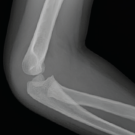

A 3-year-old boy presented to the emergency department for the fourth time in 8 days, this time for left ankle and foot swelling.